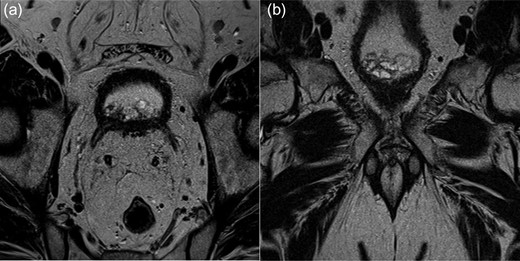

His initial investigations included a flexible cystoscopy which revealed an oedematous bladder neck with no pedunculated masses and a CT urogram (CTU) demonstrated a broad-based lobular soft tissue mass in the neck of the bladder with normal perivesical planes. Two further rigid cystoscopies were performed, however no definite lesion was visualized to biopsy or resect. In view of his abnormal CTU and negative cystoscopies, a multiparametric prostate MRI was arranged. The MRI described non-specific dependent signal abnormality at the base of the bladder neck (trigonal area) with associated mucosal irregularity (Fig. 1).

MRI multiparametric axial (a) and coronal (b) images of an irregularity at the base of the bladder neck.